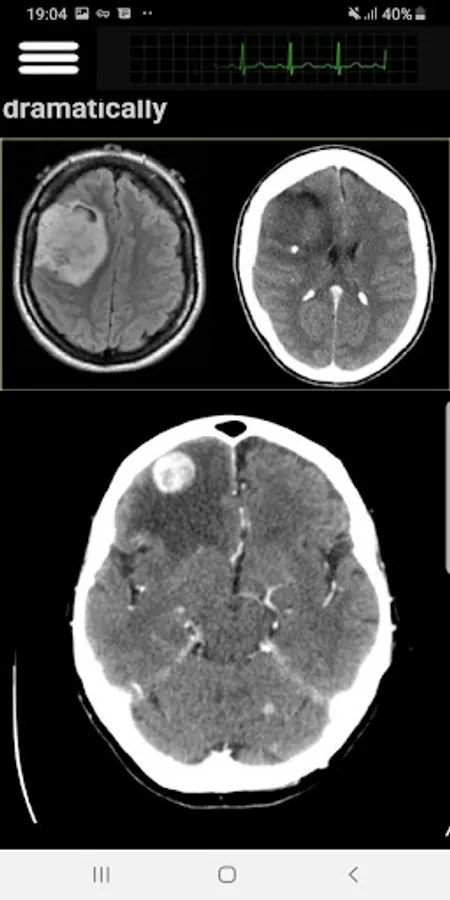

In this app, I covered the most important Head CT-Scan features that a practitioner face in his clinic or in an ER. Subjects like Hoe to read in an organize way, Blood, cisterns, Brain, Ventricles and bone.